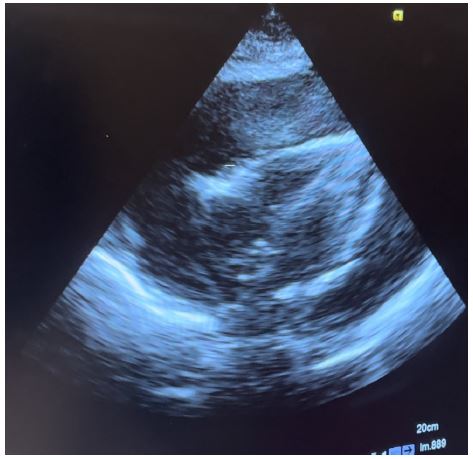

Figure 1: Subcostal echo view showing massive pericardial effusion.

Transthoracic echocardiography is the best diagnostic imaging, useful in diagnosis and management of tuberculous pericardial effusion. Echocardiography can provide an estimate of the size of effusions. Generally, the size of the effusion on echocardiography indicates the volume of pericardial fluid as follows: small (<10 mm), which corresponds to 50-100 mL pericardial fluid; moderate (10-20 mm), corresponding to 100 - 500 mL pericardial fluid and large (>20 mm), corresponding to >500 mL pericardial fluid [19] . The study of Diakité et al. showed 18% of moderate abundance and 81% of high abundance among 49 cases of tuberculous pericarditis [6].